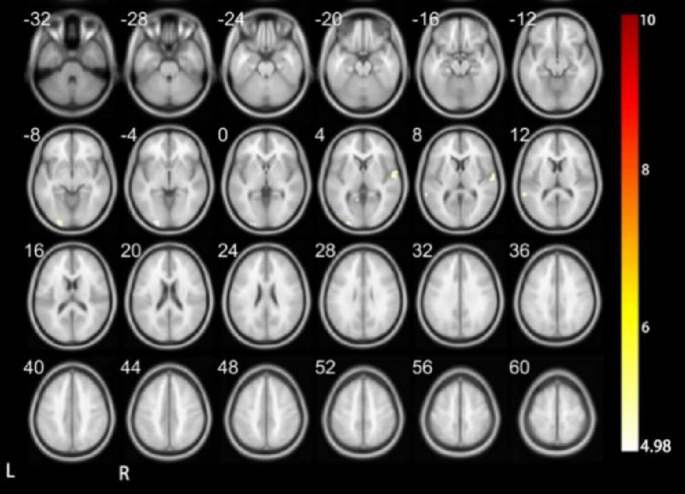

The comparative analysis presented in Figs. 8 and 9; Tables 8 and 9 between DC and HC during specific cognitive tasks reveals a fascinating divergence in neural activation patterns. This divergence underscores the adaptive neuroplasticity in response to sensory loss and highlights distinct pathways for processing similar stimuli. For DC, neural activation was confined to the left middle occipital gyrus, left middle temporal gyrus, and right superior temporal gyrus. These regions are pivotal for visual and auditory processing, indicating a reliance on available sensory input for interpreting complex stimuli. In contrast, HC exhibited a broader spectrum of activation. The right Cerebellum_Crus1, left medial middle temporal gyrus, right middle occipital gyrus, right middle temporal gyrus, right middle frontal gyrus, left triangular part of the inferior frontal gyrus, and medial parietal regions are included. The activation in these areas suggests a more integrated approach to processing, utilizing both cerebellar coordination and cortical areas associated with higher-order cognitive functions.

Notably, the superior temporal gyrus was activated in DC but not in HC. This finding may reflect compensatory mechanisms in deaf children, possibly leveraging residual auditory processing capabilities or cross-modal plasticity to interpret auditory-related information. Conversely, activation in the occipital and middle temporal gyrus regions was lateralized to the left hemisphere in DC and to the right hemisphere in HC. It indicates differential engagement of visual and auditory processing networks. Furthermore, regions such as the Cerebellum_Crus1, medial occipital gyrus, middle frontal gyrus, triangular part of the inferior frontal gyrus, and medial parietal regions were not activated in DC, whereas they were in HC. This absence of activation in DC could reflect the neural reorganization or prioritization of alternative processing pathways in the absence of typical auditory input.